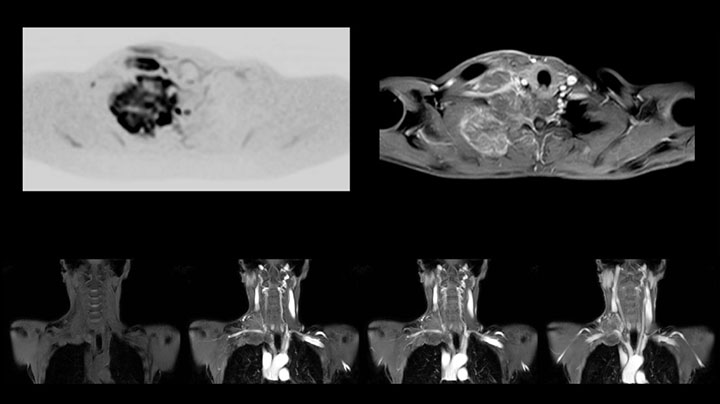

Although the area between the neck and the top of the lung is one of the most difficult areas for MRI, Prodiva 1.5T images show good quality in this 56-year-old male with Pancoast tumor on the right. mDIXON TFE images shows excellent fat suppression in the neck area and the DWI shows almost no distortion.

This patient is a 43-year-old female with a left supraclavicular nerve sheath tumor. The lesion is well visualized on the STIR VISTA images and on the MR neurography using DWIBS. The exam was performed on Prodiva 1.5T.

Acq voxel size 1.2 x 1.3 x 2.4 mm, Recon voxel size 0.7 x 0.7 x 1.2 mm, dS SENSE factor 2, scan time 5:46 min.